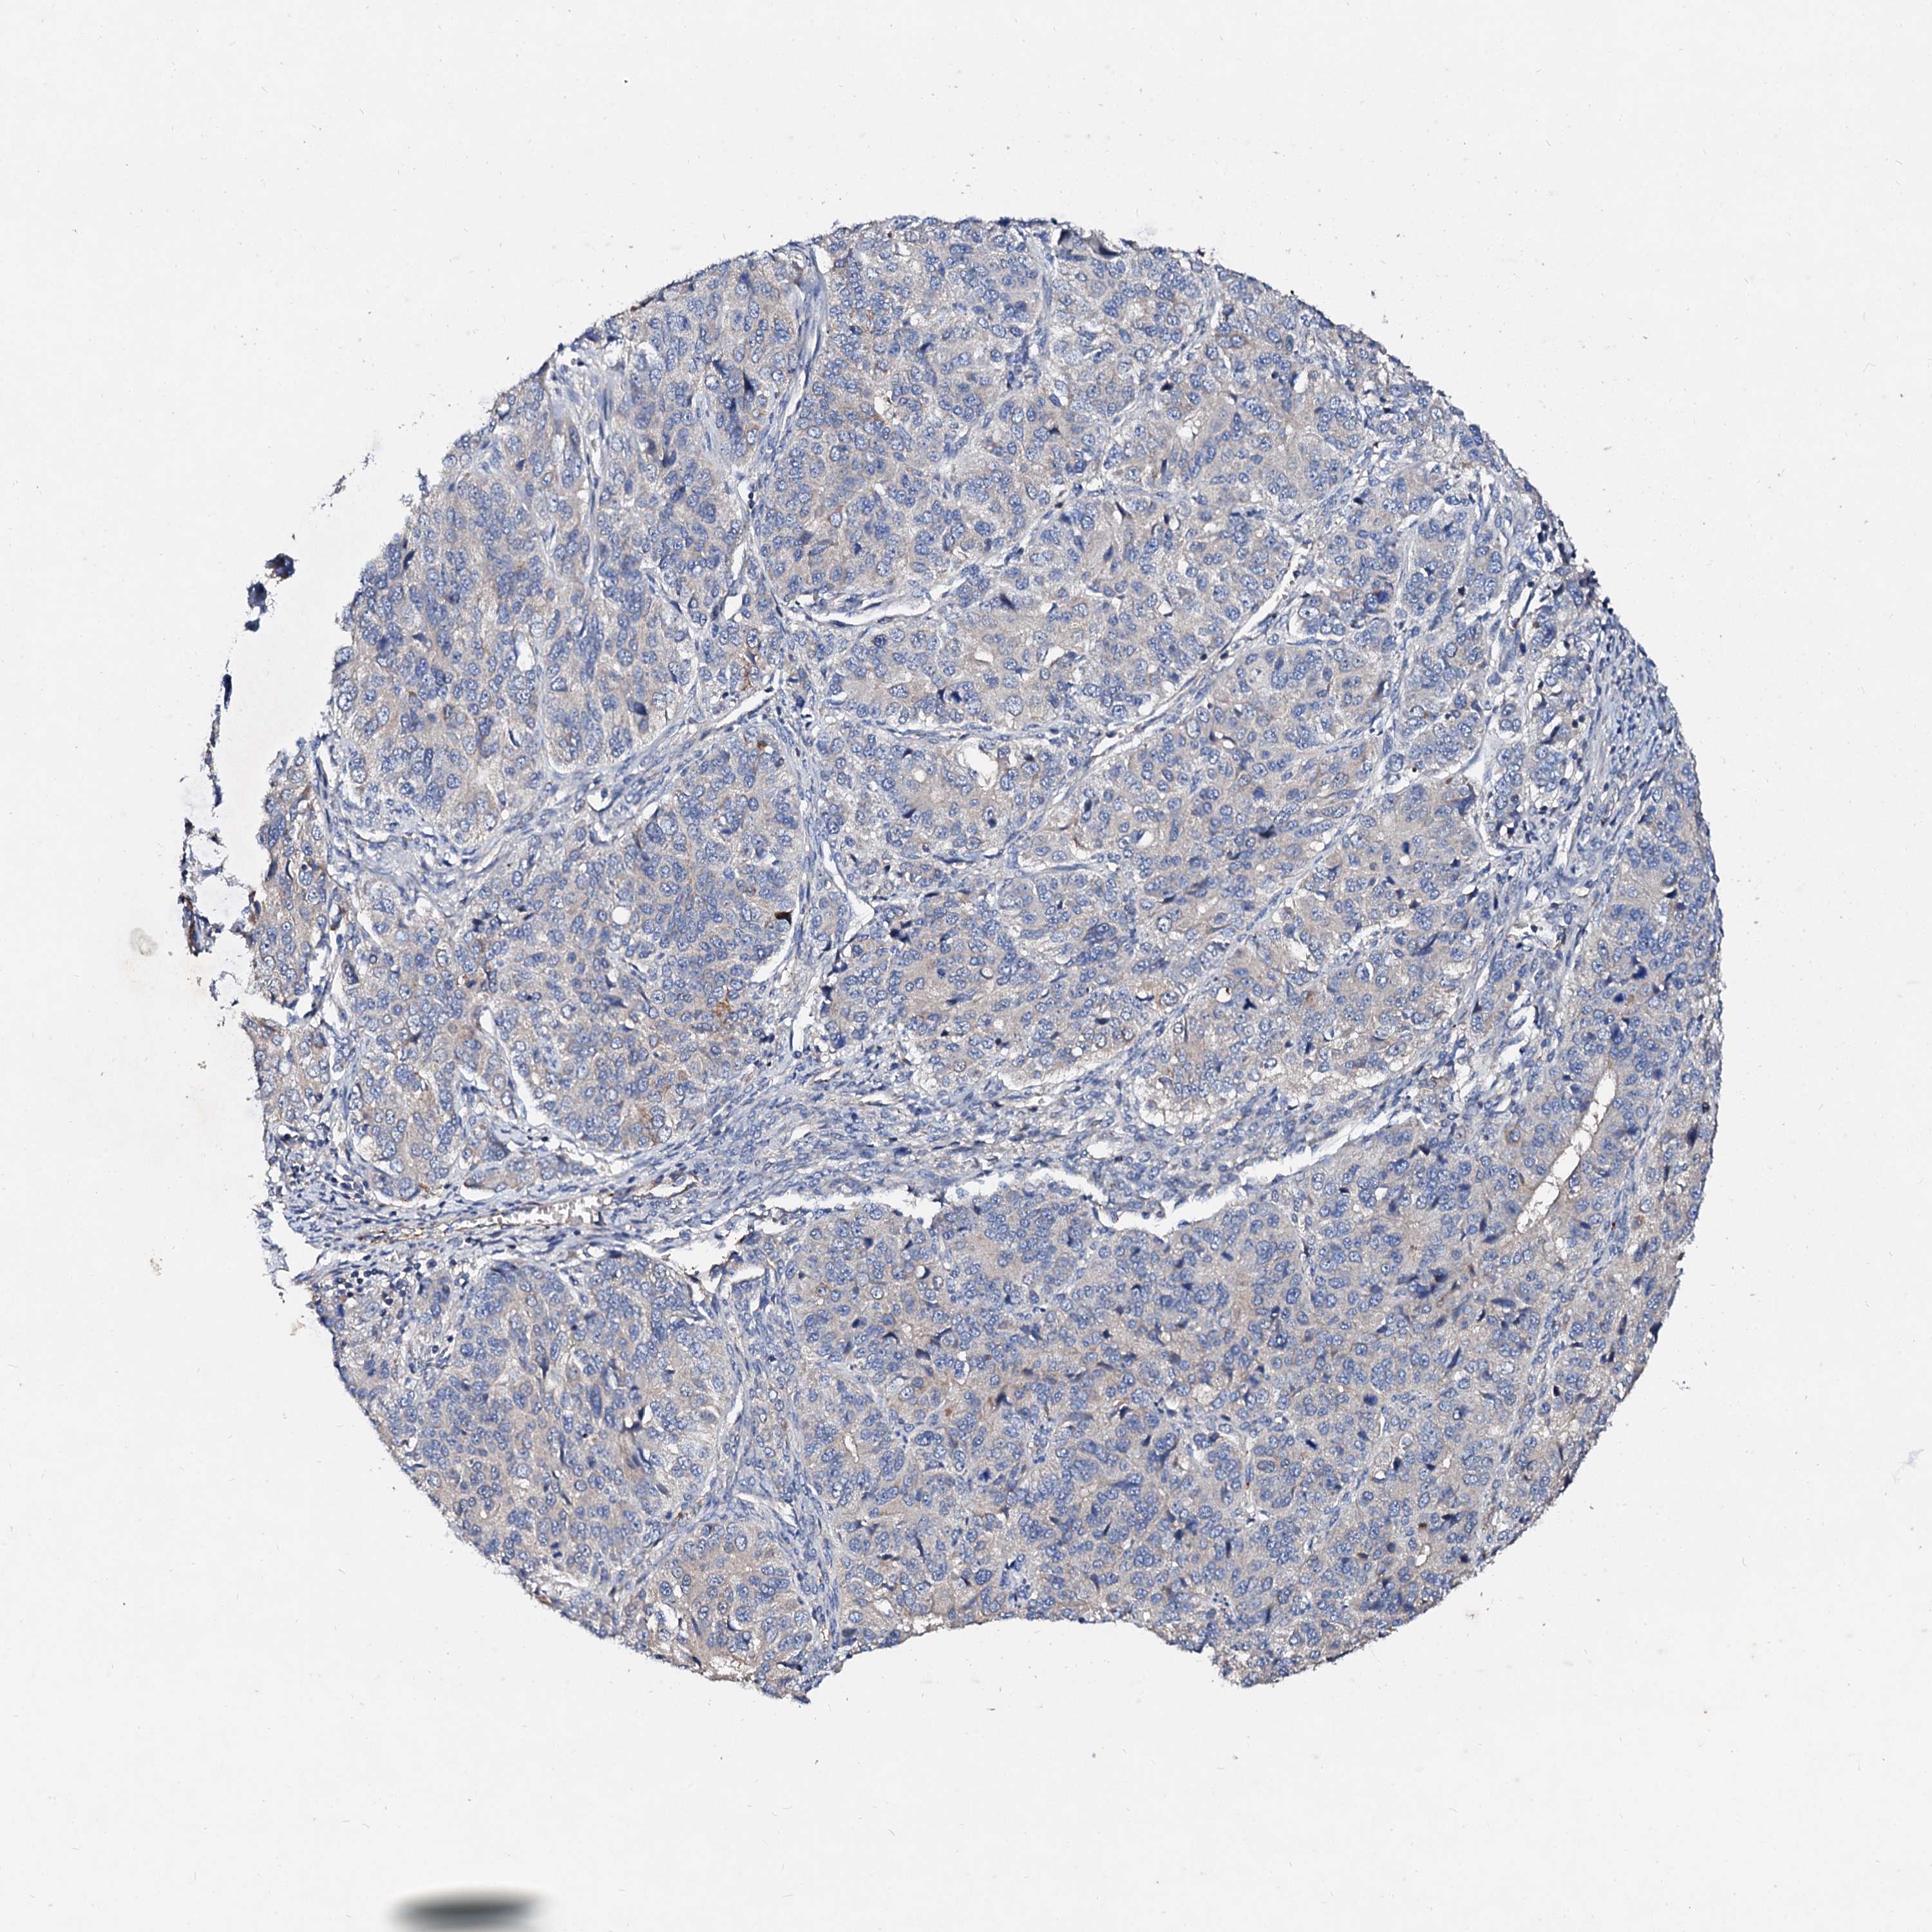

OVARIAN CANCER - Protein expressioni

A mouse-over function shows sample information and annotation data. Click on an image to view it in a full screen mode. Samples can be filtered based on level of antibody staining by selecting one or several of the following categories: high, medium, low and not detected. The assay and annotation is described here.

Note that samples used for immunohistochemistry by the Human Protein Atlas do not correspond to samples in the TCGA dataset.

Antibody stainingi

Antibody staining in the annotated cell types in the current human tissue is reported as not detected, low, medium, or high, based on conventional immunohistochemistry profiling in selected tissues. This score is based on the combination of the staining intensity and fraction of stained cells.

Each image is clickable and will lead to virtual microscopy that enables deeper exploration of all samples and also displays staining intensity scores, fraction scores and subcellular localization as well as patient and tissue information for each sample.

Antibody HPA040120

Staining

High

Medium

Low

Not detected

Intensity

Strong

Moderate

Weak

Negative

Quantity

>75%

75%-25%

<25%

None

Location

Nuclear

Cytoplasmic/membranous

Cytoplasmic/membranous,nuclear

Cystadenocarcinoma, serous, NOS

Carcinoma, endometroid

Cystadenocarcinoma, mucinous, NOS

Carcinoma, NOS